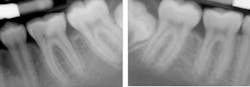

Miss Novice before the LANAP protocol.

Miss Novice showed radiographic evidence of bone regeneration seven months post LANAP. She completed orthodontics and shows stable bone three years post LANAP.

Miss Novice after the LANAP protocol.